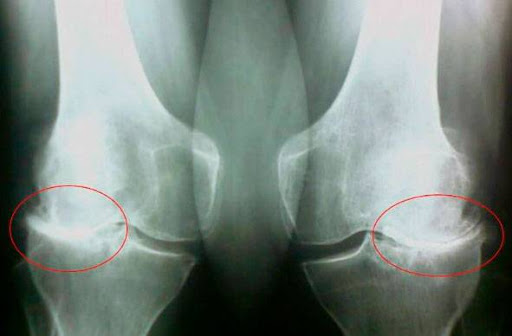

Иван Стоянов: Ами, лекарят каза, че това е краят. И не само на кариерата, но и на живота. Няма да мога да ходя, ще стана дебел, диабетът ми ще се влоши и това ще бъде гробът. Лежах в болницата, гледах тавана... Струваше ми се, че гледам капака на ковчег. Мислех, че ще умра в тази стая. Лекарят дойде отново, започна да говори за операции в Израел, в Германия, за неща, струващи СТОТИЦИ ХИЛЯДИ. После разбрах, че той просто искаше да ме измами и нямаше да ме лекува. Все пак щях да умра заради тази болка в ставите. Гледах снимките и осъзнах, че ставите ми бяха почти унищожени. Бях на прага на смъртта. Но после започна това...